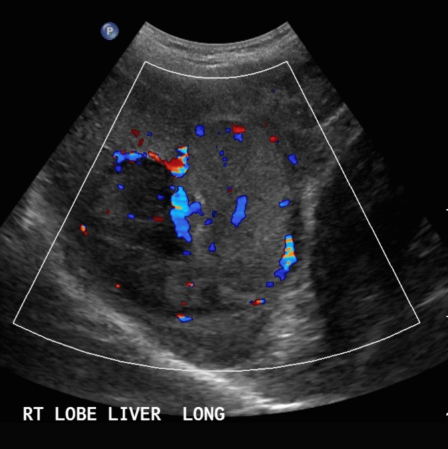

- color doppler : internal mass pattern (feeding artery)

① >5cm hcc sono finding

- massive type

- heterogenous

- irregular margin

- 괴상형, 부정형

- 중심부 응고 괴사진행( cystic change, calcification)

- color doppler: basket pattern